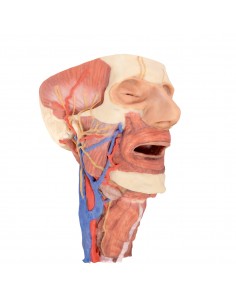

3D Anatomy 1.0 - Extremidades inferiores

Venas superficiales del miembro inferior Erler Zimmer 3D anatomy Series MP1815